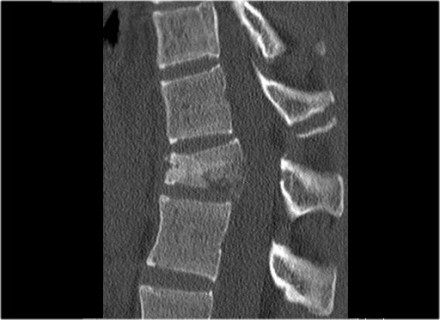

The images are of a patient with a typical bamboo spine as a result of ankylosing spondylitis.

After a fall on his back no fracture was seen on the x-rays.

However the CT shows a thin fracture line through the anterior side of the vertebral body and also through the spinous process.

Continue with the MR-images.